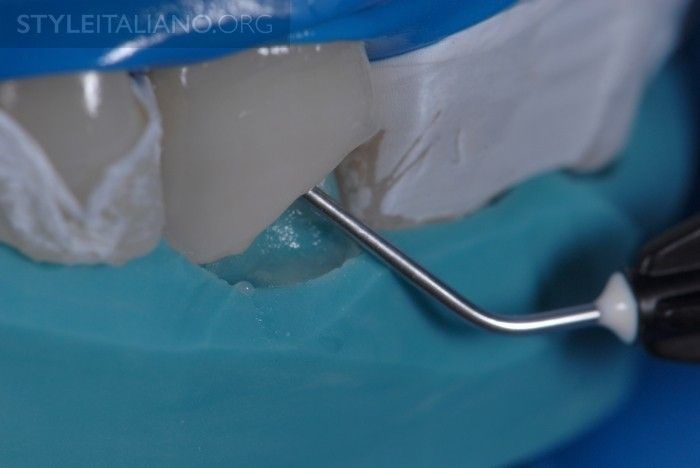

Hình 11. Tip 2. Etching qua khỏi đường bevel 2mm. Hai răng kế cận với răng trám được cách ly bởi băng cao su non. Etching vị trí răng cần trám bằng kỹ thuật selective-etch hoặc trong trường hợp này, etching men trong vòng 30 giây và ngà răng 15 giây.

Hình 12. Acid phosphoric được rửa sạch trong 15 giây. Ngà răng vẫn được giữ ẩm để giữ được độ bền dán.

Hình 13. Thực hiện kỹ thuật quét bond nhiều lớp (Single Bond, 3M ESPE) trên toàn bộ vùng răng đã được etching, và sau 30 giây, thổi hơi để làm bay hơi dung môi, keo dán còn lại là một lớp mỏng ổn định trên răng.